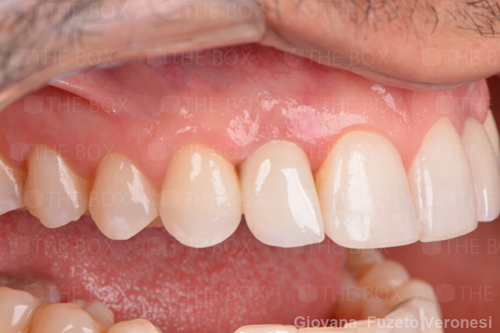

A new case was made public by Jean-Claude Imber check it out here.